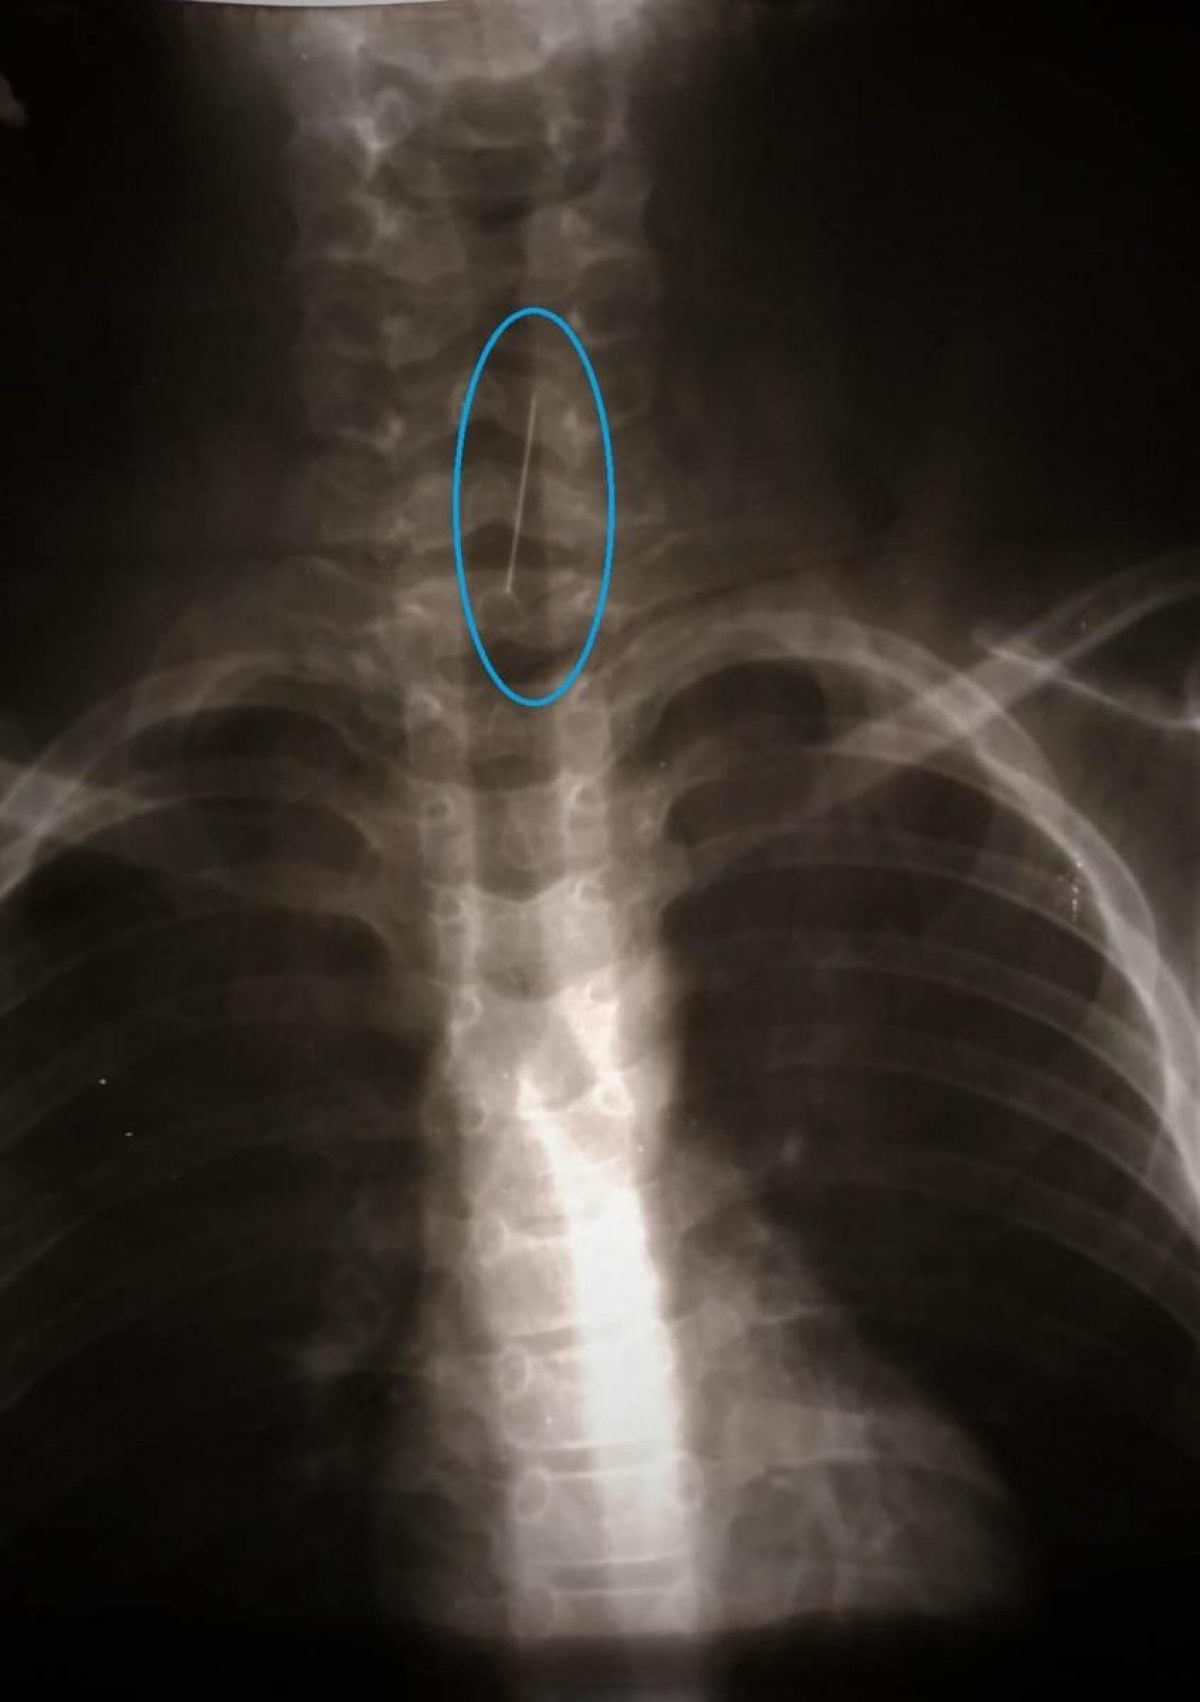

Ребенок проглотил или нет

Ребенок проглотил или нет 103 фотографий